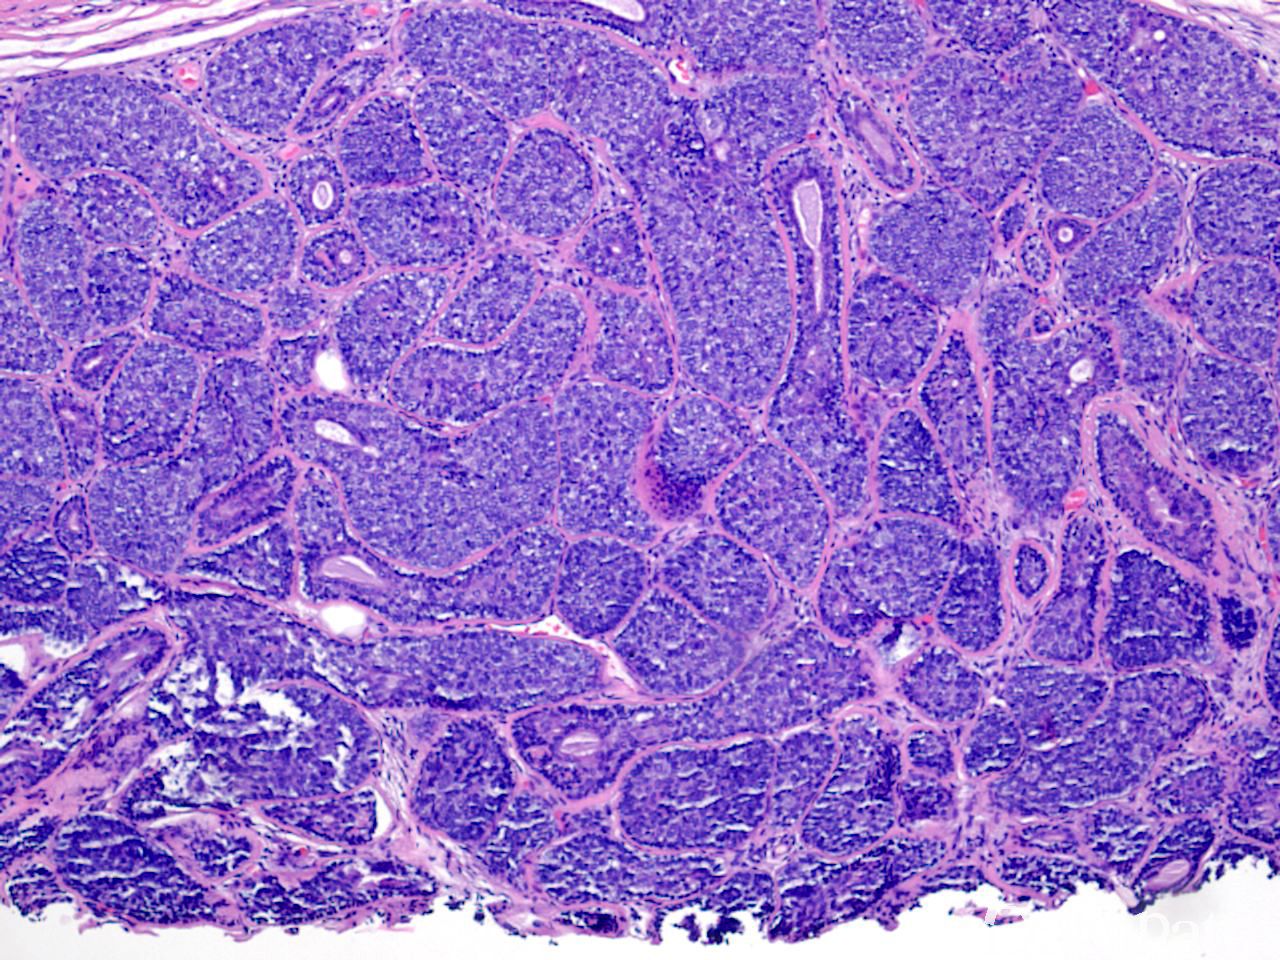

2. 镜下见形状大小不一的瘤细胞巢、团,形成拼图(七巧板样)或鹅卵石路样结构,部分区域细胞呈条索状增生;

3. 瘤细胞可分两类:一类细胞核小、色深,排列在巢团周边,另一类细胞位于细胞巢中央,染色较轻浅或胞浆透亮;

4. 细胞巢内可见小管样结构,细胞巢周围见明显的基底膜包绕。